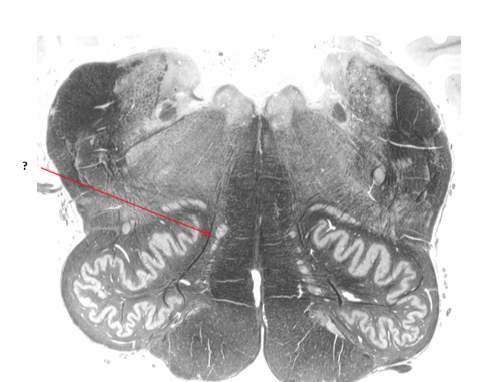

Name this and state its function within its 2 parts.

Olive.

Inferior: integrates motor and sensory function

Superior: sound localisation.